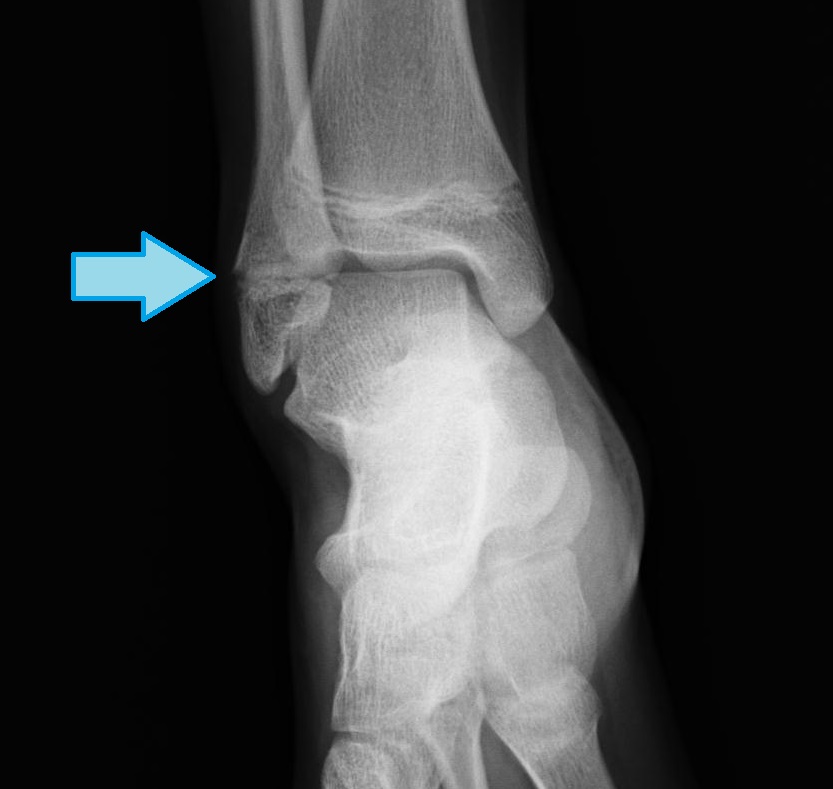

子供の足首の捻挫は骨端線損傷|にしぼり整形外科|茨城県笠間市

【症例報告】5歳 女児 脛骨遠位端骨折(子供の足首の骨折) やまもと接骨院 岐阜県笠松町・岐南町のほねつぎ・接骨院